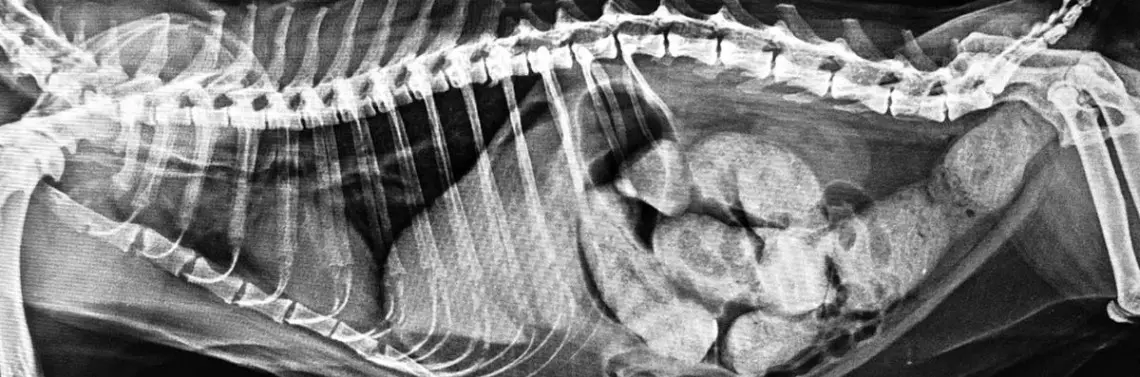

Skoro już ustaliliśmy, czym jest „ciocia Minnie”, należy również zaznaczyć, czym nie jest. Nie jest rozpoznaniem „szczęśliwego oka”, czyli ustaleniem diagnozy na podstawie pierwszej zauważonej zmiany. Nie jest to również rozpoznanie uniwersalne, czyli brak zmiany, która zwykle towarzyszy danej chorobie, nie wyklucza jej występowania. Pojęcie prawne o domniemanej niewinności oskarżonego nie ma w radiologii racji bytu! Wiele chorób ma obraz łudząco podobny do rozpoznania „cioci Minnie” innej choroby (Fot. 9A–B).

W rozumieniu rozpoznania „cioci Minnie” obraz zmian może odpowiadać jednej chorobie, natomiast to samo schorzenie może również przedstawiać się w inny sposób lub wręcz może nie być widoczne. Łatwym przykładem może być złamanie, ponieważ uwidocznienie złamanej kości oznacza jedną diagnozę, natomiast brak widocznego na radiogramie złamania nie może go wykluczyć, a jedynie zmniejszyć prawdopodobieństwo. Jednak nawet w ta...